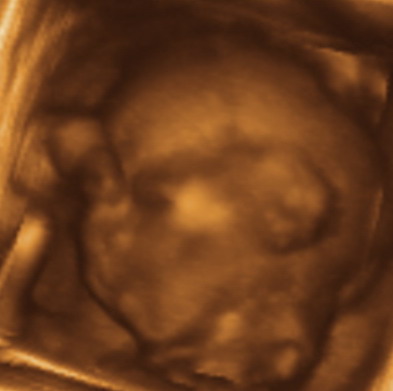

Mar nem tudtam utazas elott jonni, bocs! De teszek fel ket kepet, remelem kiveszitek hogy mit lattok... Ja, es garatulalaok a most mar "tuti hogy kislany"-odhoz!!! Nagyon arik a kepek amiket feltettel, hihetetlen, hogy 4 hettel vagytok idosebbek mint mi es mennyire masok a fotok!

Nekunk remekul sikerult ez a koltozessel, utazassal es nyaralassal teli 3 het, bar mostanra nagyon elfaradtunk. Voltunk 3D-4D-s uh-n meg indulas elott, amit nagyon elveztunk. Kepzeljetek, nyitva volt a szeme, csuklott es ott sem volt hajlando megallni egy pillanatra sem. A kepek amiket kaptunk nem lettek tul jok, de igazabol mi most nem is a sztarfotok miatt mentunk, hanem szerettuk volna meg egyben latni, igy 20 hetesen. Viszont az egesz videon van, mar nem tudom hanyszor neztuk meg :) . A felvetelek vszleg csak nekunk szepek, tunderiek es edesek, lehet hogy ti majd csak egy kis ufonautat lattok benne, de hat ez van, ebben a korban kb ilyen kepekre lehet szamitani, bar van aki szerencsesebb. Mindenkepp akarok meg egyszer menni 3D-re, amikor mar nagyobb lesz, valamikor 30 het kornyeken. Nagyon nagy elmeny volt, ajanlom mindenkinek! A pocakom elkezdett szeduletes iramban noni, elkepeszto mennyit valtozik egy het alatt. Minden heten keszitunk rola kepet (ezt egyebkent mindenkinek ajanlom, ha meg nem csinalja) es nagyon muris egymas melle tenni oket... Szoval a pocak feszul, huzodik rendesen, de csak ritkan kemenyedek be. Diohejban ennyi, most mar gyakrabban fogok jonni, mert lassan vegzunk a pakolassal is.

Ez a feje es a jobb karja/keze, talan felismeritek...

Kép